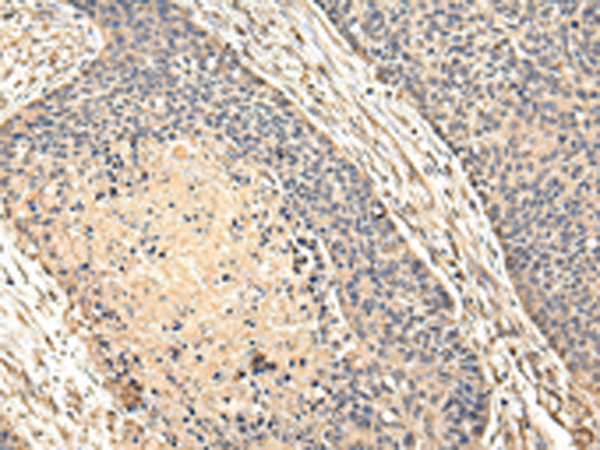

分类: 科研抗体货号: P02100别名:应用: WB,IHC反应种属: Human, Mouse

分类: 科研抗体货号: P02020别名: Ipi3; R32184_1应用: WB,IHC反应种属: Human, Mouse

分类: 科研抗体货号: P01920别名: HAT应用: WB,IHC反应种属: Human, Rat

分类: 科研抗体货号: P02094别名: EMC5; TMEM32应用: WB,IHC反应种属: Human, Mouse, Rat

分类: 科研抗体货号: P01915别名: CAPH2; MT-SP2; TMPRSS3应用: WB,IHC反应种属: Human, Mouse

分类: 科研抗体货号: P02005别名:应用: WB,IHC反应种属: Human, Mouse, Rat

分类: 科研抗体货号: P02092别名: NAAGS; FAM80B; NAAGS-I应用: IHC反应种属: Human, Mouse

分类: 科研抗体货号: P02085别名: ECO; ICK; MRK; LCK2; EJM10应用: IHC反应种属: Human, Mouse, Rat

分类: 科研抗体货号: P02002别名:应用: WB,IHC反应种属: Human, Mouse